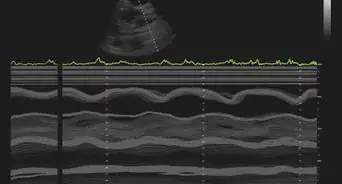

- Echocardiography uses sound waves to detect the structure and motion of the heart. For this procedure, you would receive a transthoracic echocardiogram, not a transesophageal echocardiogram. A device is moved over your chest while you remain motionless. The images it gathers can show the thickness of the heart and the way it pumps, as well as assess the function of the valves that may be contributing to the heart failure. An echo can also help your doctor figure out if the heart has poor blood flow or any damage to the muscle.[16]